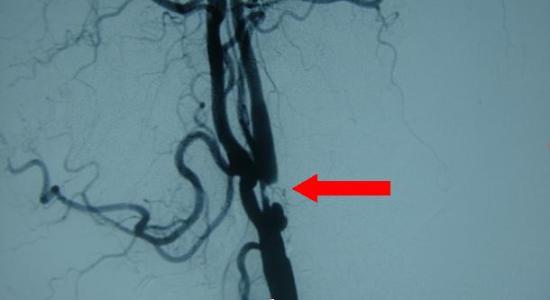

摘  要: 目的 观察彩色多普勒超声与经颅多谱勒超声(TCD)联合应用诊断颈内动脉(ICA)狭窄的价值。方法 选择 2017 年 2 月至 2018 年 2 月于我院就诊的 ICA 狭窄患者,共 64 例,均给予彩色多普勒超声、TCD 和联合检查,根据结果分为 A 组、B 组和 C 组,比较三组患者的诊断结果。结果 联合方法诊断率明显比单一方法诊断率高,具有统计学意义(P< 0.05)。结论 在诊断 ICA 狭窄时,联合彩色多普勒超声与 TCD 检查,能够极大的提高临床诊断符合率,值得临床应用与推广。

1.2.4DSA 检查:采用LCE 和型C 型壁(美国GE 公司生产), 所选用的对比剂为欧乃源克,采用 Sedingep’s 技术,安放导鞘 4-5F,在导丝辅助下采用猪尾造影在主动脉弓中植入导管头部,然后进行主动脉弓造影,然后对普通造影管进行改造, 对颈动脉和椎动脉进行选择性造影 [2]。

DSA:48 例单侧狭窄、12 例闭塞;2 例双侧狭窄;4 例一侧闭塞一侧狭窄,。双侧狭窄共56 支,16 支闭塞,56 支正常。